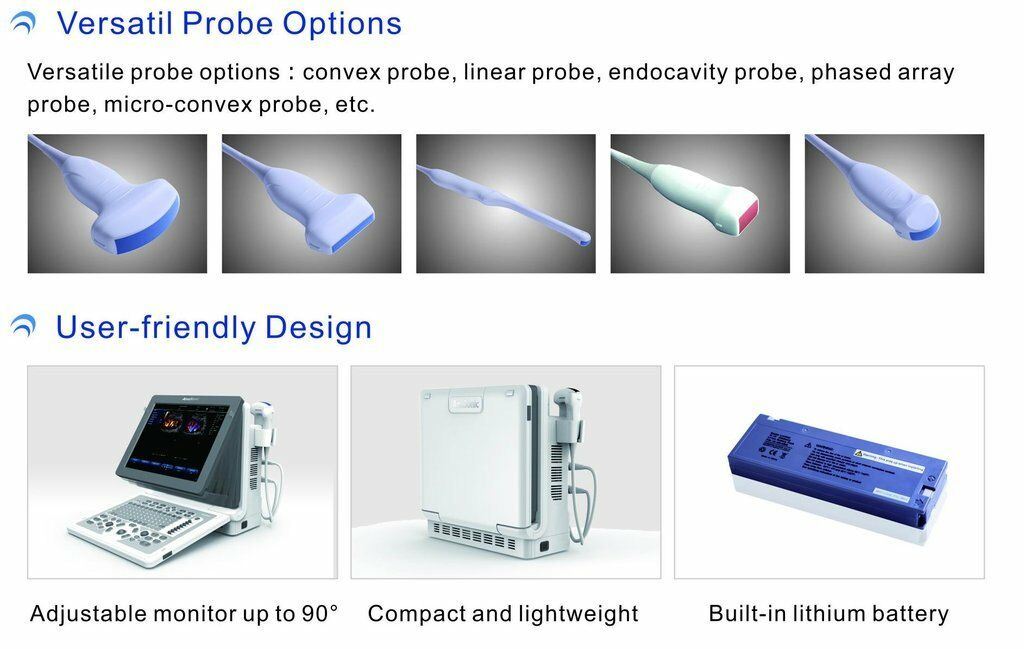

DIAGNOSTIC ULTRASOUND MACHINES FOR SALE